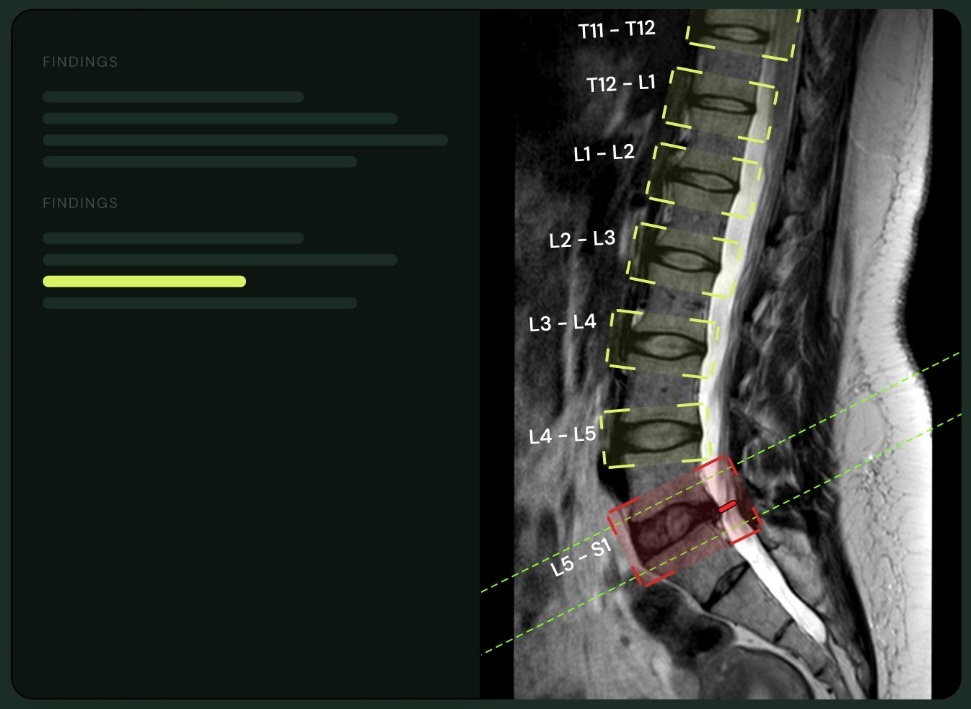

Old dot-phrase systems gave you a paragraph you still had to edit. Medsee gives you the scoring system itself, as a form. Pfirrmann 1 to 5 is a selector. Disc morphology is a toggle. Cord compression has its own red-flag section. You read the scan, grade what you see, and the report is written from your selections.

One-click Pfirrmann 1 to 5 grading per disc level, with disc morphology and stenosis grade alongside.

Pfirrmann, disc morphology, stenosis grade, canal narrowing, cord signal, and a red-flag section for cord compression.